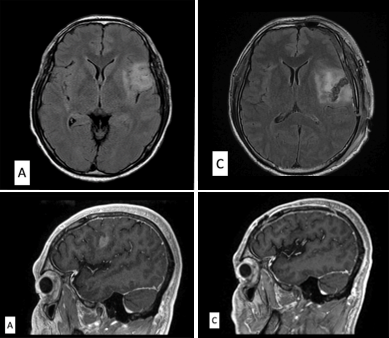

The location of the speech area in the brain may be different or located in several sites in patients who speak multiple languages, and knowledge of potential eloquent sites is important to preserve language function. In this paper, we performed a systematic review of cortical mapping during awake brain tumor surgery in multilingual patients. We also presented sample cases of glioma, a type of brain tumor, located in the speech area of the brain in two multilingual patients, one Filipino and one Indian.

The systematic review yielded seven studies, with a total of 25 multilingual brain tumor patients who underwent awake brain mapping. Most (52 percent) were trilingual, while 20 percent were quadrilingual and 28 percent were pentalingual. All tumors were left-sided, mostly in the frontal lobe, and most were gliomas. The brain mapping findings were variable. Some authors reported a greater number of cortical sites for the first language compared to others. Others found that the first and second languages shared cortical sites whereas the third and subsequent languages were located in distant sites. A larger number of cortical areas were also activated for languages that were learned later in life. Cortical mapping in multilingual brain tumor patients had mixed results in terms of the location and number of language areas, as well as language disturbance and recovery after surgery. These findings may influence management of tumors in the speech area but emphasize the need to tailor surgical approaches and intraoperative testing to each individual patient.